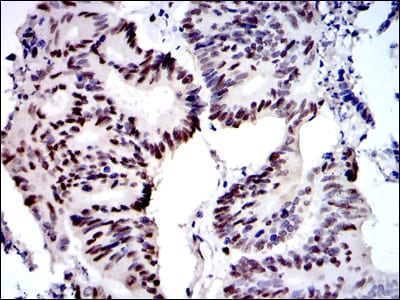

| IHC | 1/200 - 1/1000 | Human,Mouse,Rat |

In clinical settings, MCM2 antibodies are employed in immunohistochemistry (IHC) to assess cell proliferation in cancers (e.g., breast, prostate, and gliomas) and to distinguish between benign and malignant lesions. Additionally, they are used in basic research to study replication mechanisms, checkpoint regulation, and genomic stability. Recent studies also explore MCM2’s potential as a therapeutic target in anticancer strategies.